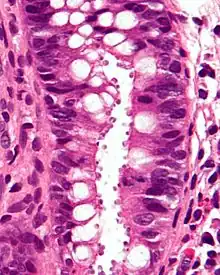

| Micrograph showing cryptosporidiosis. The cryptosporidium are the small, round bodies in apical vacuoles on the surface of the epithelium. H&E stain. Colonic biopsy. | |

Other staining techniques include acid-fast staining,[28] which will stain the oocysts red.[27] One type of acid-fast stain is the Kinyoun stain.[23] Giemsa staining can also be performed.[24] Part of the small intestine can be stained with hematoxylin and eosin (H & E), which will show oocysts attached to the epithelial cells.[27]